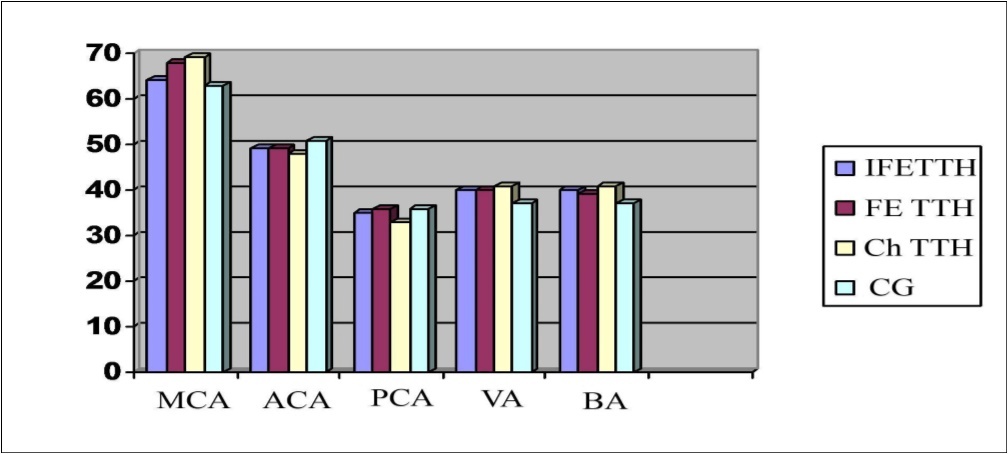

The asymmetry of the maximum systolic blood flow velocity (Vs) in the paired arteries within 20-30% was considered a violation of cerebral hemodynamics, which was detected in 38.7% of patients. An increase in Vs was noted in MCA in patients with Ch TTH and FE TTH compared with the control group (Figure 1, Figure 2A and B).

Figure 1.Parameters of Vs (cm/c) in the main cerebral arteries in a patients with TTH.

Infrequent episodic (IFE) TTH were recorded in 86.4% of cases, frequent episodic (FE) — in 88.9%, and chronic (Ch) TTH — in 81.6% of cases. Bilateral TTH was noted in 39.2%, frontal localization - in 35.6%, in the occipital region - in 25–7% of cases. The asymmetry of the maximum systolic blood flow velocity (Vs) in the paired arteries within 20-30% was considered a violation of cerebral hemodynamics, which was detected in 38.7% of patients. An increase in Vs was noted in all cerebral vessels, especially in patients with FE TTH and chronic Ch TTH compared with the control group.